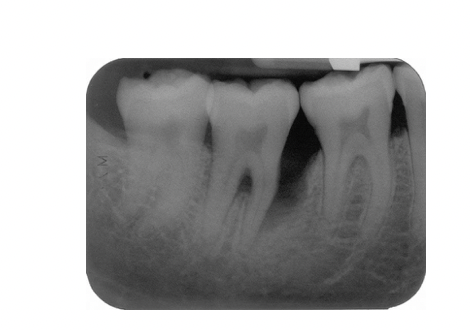

Describe 2 patterns of bone loss evident in this radiograph?

A

• Horizontal and vertical

What explains the development of bone loss on the mesial aspect of the lower right second premolar?

• Presence of plaque accumulation (scalloping) in the distal aspect of the tooth , the canal curvature may have acted as a plaque trap

Following hygiene phase therapy this patient’s oral hygiene was excellent but pockets of >6mm persisted in the lower right quadrant. Open flap debridement was performed

What feature of this patient’s disease which is on the radiograph is most likely to limit the success of this treatment and why?

Fucration involvement due to bone loss making access for cleaning difficult leading to poor prognosis of tooth